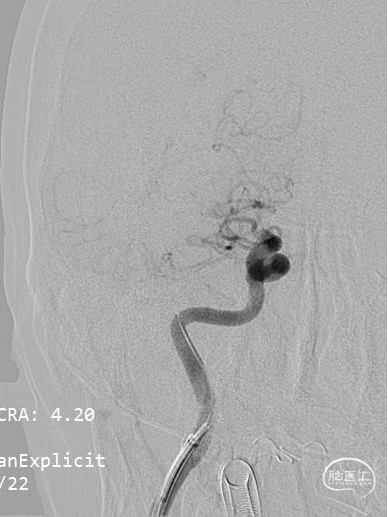

一次支架取栓后血管完全通畅,达到mTICI 3级。

可见取出血栓量较大,在支架远端抓捕篮内有部分细小血栓被成功捕获。

术后即刻影像可见血管完全通畅,达到mTICI 3级。